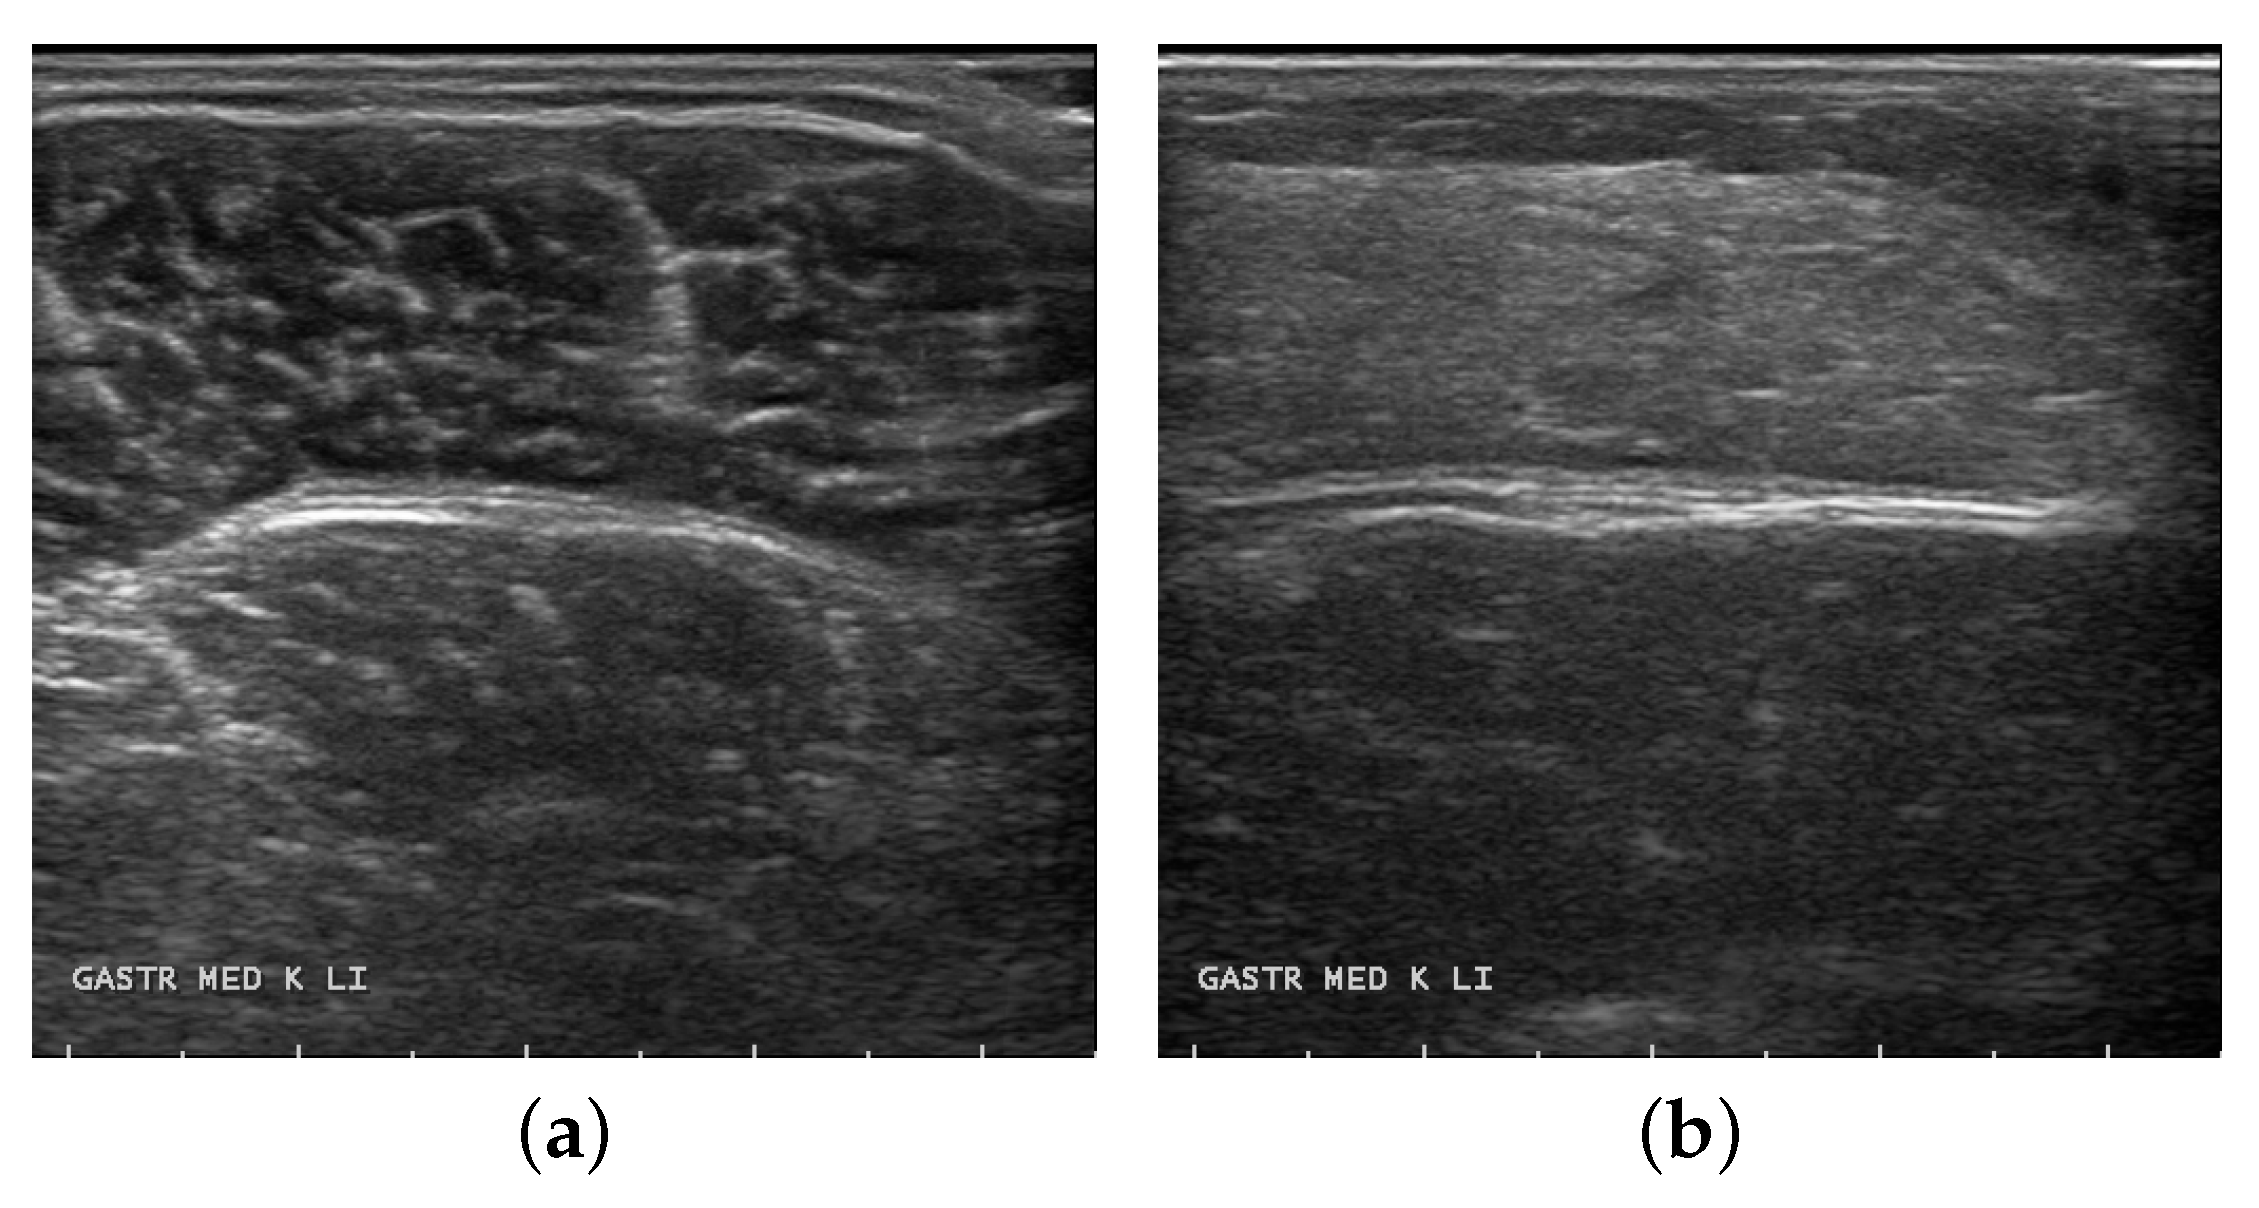

The quantitative analysis of longitudinal musculoskeletal ultrasound images enables us to obtain important parameters that reflect the state of the muscle, including pennation angle, muscle thickness, and fiber length. These morphological characteristics are directly related to the mechanical properties of muscle tissue and can guide rehabilitation science treatments such as muscle rehabilitation training and prosthetic control [3]. The analysis of transverse musculoskeletal ultrasound images enables the acquisition of muscle cross-sectional area (CSA) between deep and superficial aponeurosis and the early abnormal diagnosis of neuromuscular diseases. The correct segmentation of the muscle CSA is a key step in the assessment of the muscle condition. It reveals the strength level of muscles [4] and reflects the health level of sports and the severity of disease. In transverse musculoskeletal ultrasound images, normal muscles have moderate echogenicity, with reticular and banded separation visible in the middle of the deep tendon membrane, as well as speckled moderate to high echogenicity [5]. In contrast, pathologic muscles are affected by increased fat replacement and the presence of connective tissue, which can result in increased echogenic reflections that appear faintly textured, cloudy, or hairy and glassy [6]. This phenomenon has been found to correlate with the staging of neurological disease [7].

The samples used in experiments were from the public datasets of transverse musculoskeletal ultrasound images in the paper by Marzola et al. [25]. The datasets were acquired during routine clinical practice, at the Radboud University Medical center. Images were scanned transversely by experienced muscle neurodiagnostic technicians using ultrasound equipment on muscle tissue. Data were analyzed from multiple subjects with images of different parts of the muscle and, for each subject, three or four transverse ultrasound images of skeletal muscle were acquired as required by the clinical protocol. The medial gastrocnemius muscle ultrasound images, which are of more clinically generalizable value in this dataset, were selected for our experiments. Of these samples, 349 images were from diseased subjects and another 1478 were from healthy subjects, for a total of 1827 images. Healthy muscles show moderate echogenicity in transverse ultrasound images of muscle, with reticular and band-like separations and speckled echogenicity in the middle of deep and superficial tendon membranes, which are myofascicular and intramuscular structures. In contrast, the diseased muscles showed blurred texture and echogenic enhancement between the deep and superficial tendon membranes, with a cloudy or hairy glass-like morphology. Figure 5 shows the transverse muscle ultrasound images of healthy and diseased subjects, respectively.

Figure 5. Samples of transverse ultrasound muscle images in healthy (a) and diseased (b) subjects.